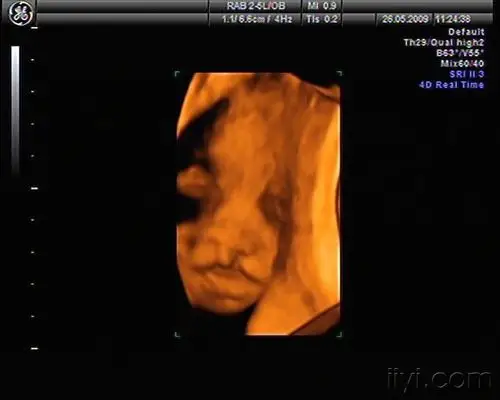

四维的图片能不能看出唇裂呢?

胎儿双侧唇裂四维成像图

四维彩超显示唇裂,结果会出错吗?